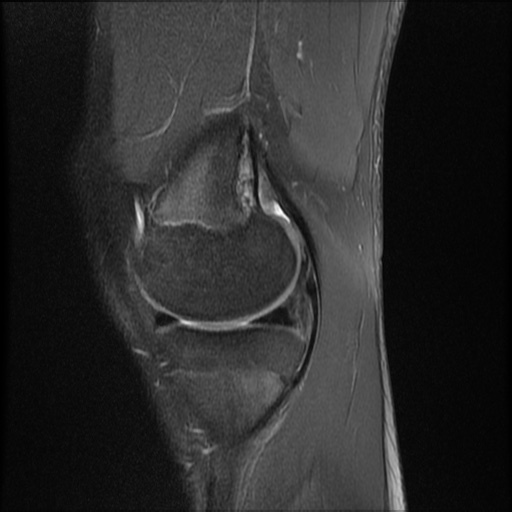

Lateral patellar dislocation

THINGS TO ALWAYS mention in patella injury

• Injury to MPFL

• oestochondral fracture

• patella alta - insall salvati ratio

• should be <1.3.

• Blackburn peel ratio

• normal =0.8

• Patella alta > 1

• Inc TTTG trasnlation distance

• Femoral trocklea displasia

Lateral patellar dislocation refers to lateral displacement followed by dislocation of the patella due to disruptive changes to the medial patellar retinaculum.

Patellar dislocation most commonly results from a twisting motion, with the knee in flexion and the femur rotating internally on a fixed foot (valgus-flexion-external rotation) 1.

Radiographic features

Plain radiograph

lateral displacement of patella noted on skyline projection

joint effusion

sliver sign

MRI

The following features are noted:

medial retinacular abnormalities (ranging from strain to complete disruption) with adjacent periligamentous oedema and haemorrhage

lateral displacement of patella (not necessarily seen in transient dislocation)

medial patellar contusion +/- corresponding lateral femoral condyle contusion

The presence of an abnormal medial patellar retinaculum should suggest the diagnosis of transient lateral patellar dislocation 1.

The images should be scrutinized for the presence of chondral or osteochondral injury, especially if displaced as an intra-articular body, as this may affect surgical management.

The trochlear groove and patella may have abnormal morphology that predisposes to patellar dislocation.